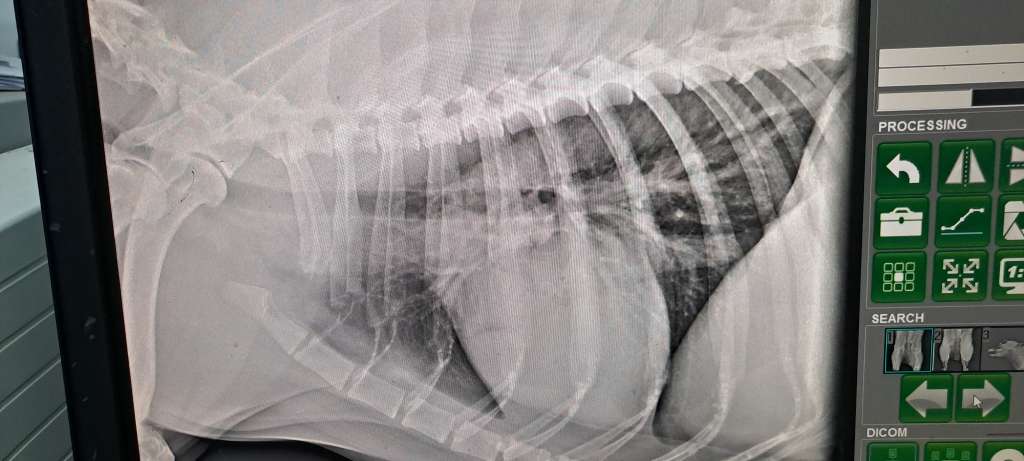

Discovering that your dog has a tumor is a devastating moment for any pet owner. In Arya’s case, the journey to a correct diagnosis was filled with confusion, delays, and emotional struggle. Here, I want to share the full story of how we went from a strange swelling under the tongue to a confirmed case of fibrosarcoma in the jaw.

The Shock During Surgery

While attempting to remove the mass, the surgeon discovered something unexpected and deeply concerning:

“The tumor is stuck to the jawbone. I can’t fully remove it without damaging the jaw.”

So instead of removal, he carefully took a biopsy sample and sent it to the lab for analysis.

The Diagnosis: Oral Fibrosarcoma in the Lower Jaw

After several anxious days waiting for the lab results, the surgeon confirmed it:

“Your dog has oral fibrosarcoma attached to her lower jawbone.”

It was a difficult moment. I was flooded with emotion, guilt, and confusion. But at least now we had an answer.